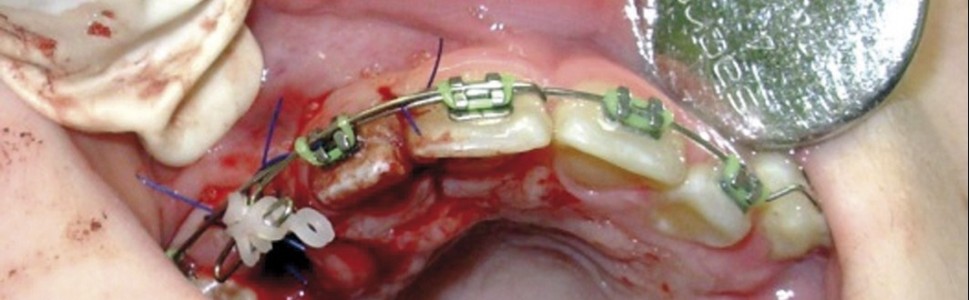

Upper canine impaction is particularly problematic both for aesthetic reasons as well as because of its impact on occlusion, the shape of the dental arch, and the patient's speech. Impaction affects mandibular canines much more rarely than maxillary canines and because of the lesser role played by mandibular canines the problem sometimes goes unnoticed for a long time. The present study describes two cases involving impacted canines – both maxillary and mandibular – treated surgically and orthodontically. The impacted maxillary canine of one of the treated patients was brought to the dental arch using the closed eruption method while the second was treated surgically with the open window technique.

Upper canine impaction is particularly problematic both for aesthetic reasons as well as because of its impact on occlusion, the shape of the dental arch, and the patient's speech. Impaction affects mandibular canines much more rarely than maxillary canines and because of the lesser role played by mandibular canines the problem sometimes goes unnoticed for a long time. The present study describes two cases involving impacted canines – both maxillary and mandibular – treated surgically and orthodontically. The impacted maxillary canine of one of the treated patients was brought to the dental arch using the closed eruption method while the second was treated surgically with the open window technique.